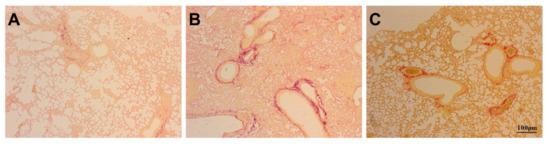

Background: Mesenchymal stem cell (MSC) intervention has been associated with lung protection. We attempted to determine whether mouse gingival-derived mesenchymal stem cells (GMSCs) could protect against bleomycin-induced pulmonary fibrosis. Methods: Mice were divided into three groups: control (Con), bleomycin (Bl), and bleomycin + MSCs (Bl + MSCs). Mice were treated with 5 mg/kg bleomycin via transtracheal instillation to induce pulmonary fibrosis. We assessed the following parameters: histopathological severity of injury in the lung, liver, kidney, and aortic tissues; the degree of pulmonary fibrosis; pulmonary inflammation; pulmonary oedema; profibrotic factor levels in bronchoalveolar lavage fluid (BALF) and lung tissue; oxidative stress-related indicators and apoptotic index in lung tissue; and gene expression levels of IL-1β, IL-8, TNF-α, lysophosphatidic acid (LPA), lysophosphatidic acid receptor 1 (LPA1), TGF-β, matrix metalloproteinase 9 (MMP-9), neutrophil elastase (NE), MPO, and IL-10 in lung tissue. Results: GMSC intervention attenuated bleomycin-induced pulmonary fibrosis, pulmonary inflammation, pulmonary oedema, and apoptosis. Bleomycin instillation notably increased expression levels of the IL-1β, IL-8, TNF-α, LPA, LPA1, TGF-β, MMP-9, NE, and MPO genes and attenuated expression levels of the IL-10 gene in lung tissue, and these effects were reversed by GMSC intervention. Bleomycin instillation notably upregulated MDA and MPO levels and downregulated GSH and SOD levels in lung tissue, and these effects were reversed by GMSC intervention. GMSC intervention prevented upregulation of neutrophil content in the lung, liver, and kidney tissues and the apoptotic index in lung tissue. Conclusions: GMSC intervention exhibits anti-inflammatory and antioxidant capacities. Deleterious accumulation of neutrophils, which is reduced by GMSC intervention, is a key component of bleomycin-induced pulmonary fibrosis. GMSC intervention impairs bleomycin-induced NE, MMP-9, LPA, APL1, and TGF-β release. Full article

Figure 1